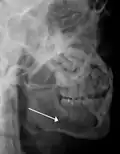

Panoramic radiograph of a simple mandible fracture of the right mandibular body, minimally displaced. Note that the teeth to the left of the fracture do not touch -

lateral oblique image demonstrating a fractured mandible.